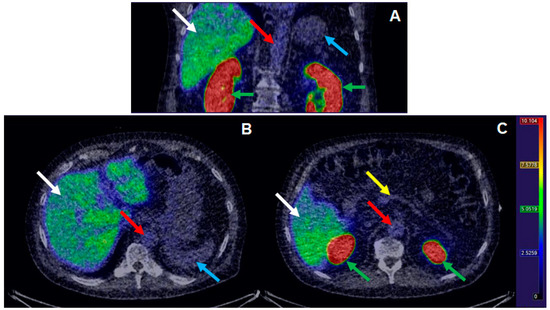

3.3. Clinical Examination